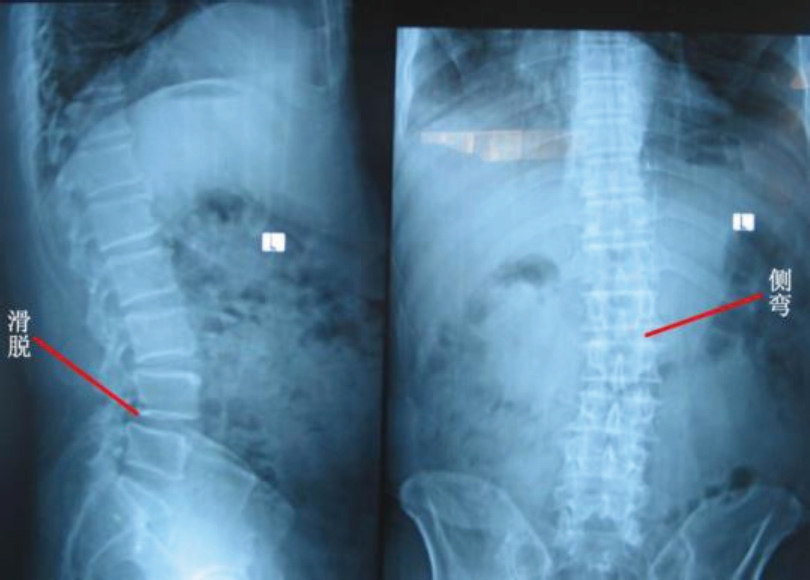

答:腰椎的稳定性靠相互关联的两个部分来维持,就如同高耸入云的金属塔架和固定拉线一样的关系(图9),即脊柱各椎体本身骨关节的完整性和与其周围肌肉韧带的协调及对称性。无论哪一部分受损或功能发生障碍,都会产生腰椎节段性不稳,继而使得椎体之间的关节在正常负荷情况下不能保持生理状态的对合关系,引起脊椎的松动、失稳,甚至出现椎体旋转位移征象(图10),伴随出现腰腿酸痛等一系列症状,因其尚无椎弓峡部崩裂(完整性还在),故又称之为“假性腰椎滑脱”(图11)。

在假性滑脱的基础上,如果继续发展下去,腰椎在发生了滑脱的同时并有椎弓峡部的不连(断裂)则称作“真性滑脱”(图5、图11 的B 和C)。临床上无论是真性腰椎滑脱还是假性腰椎滑脱,患者都可能会有下腰痛,伴或不伴有神经刺激、腰椎活动受限等症状。